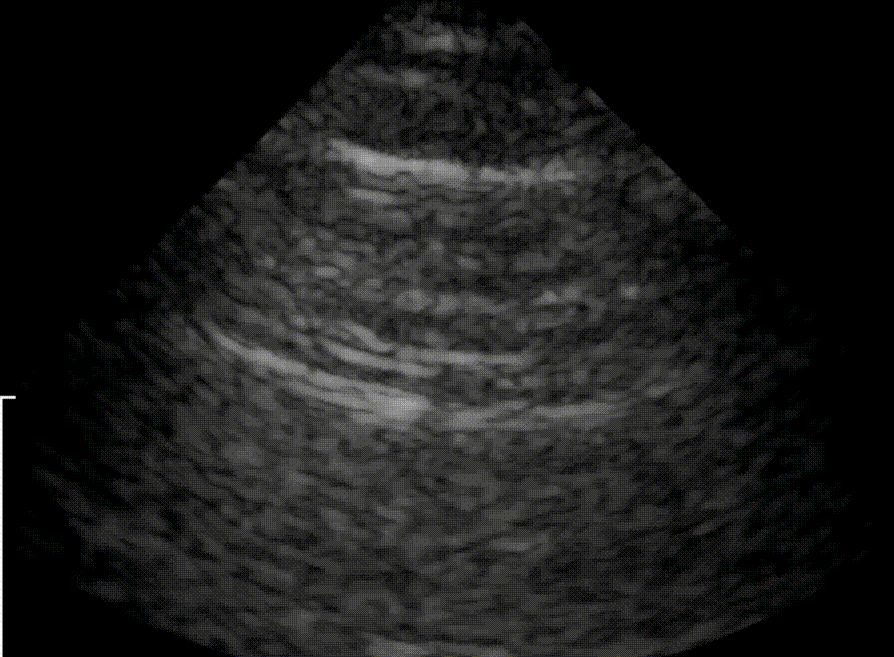

View US images that rule in or rule out a pnuemothorax